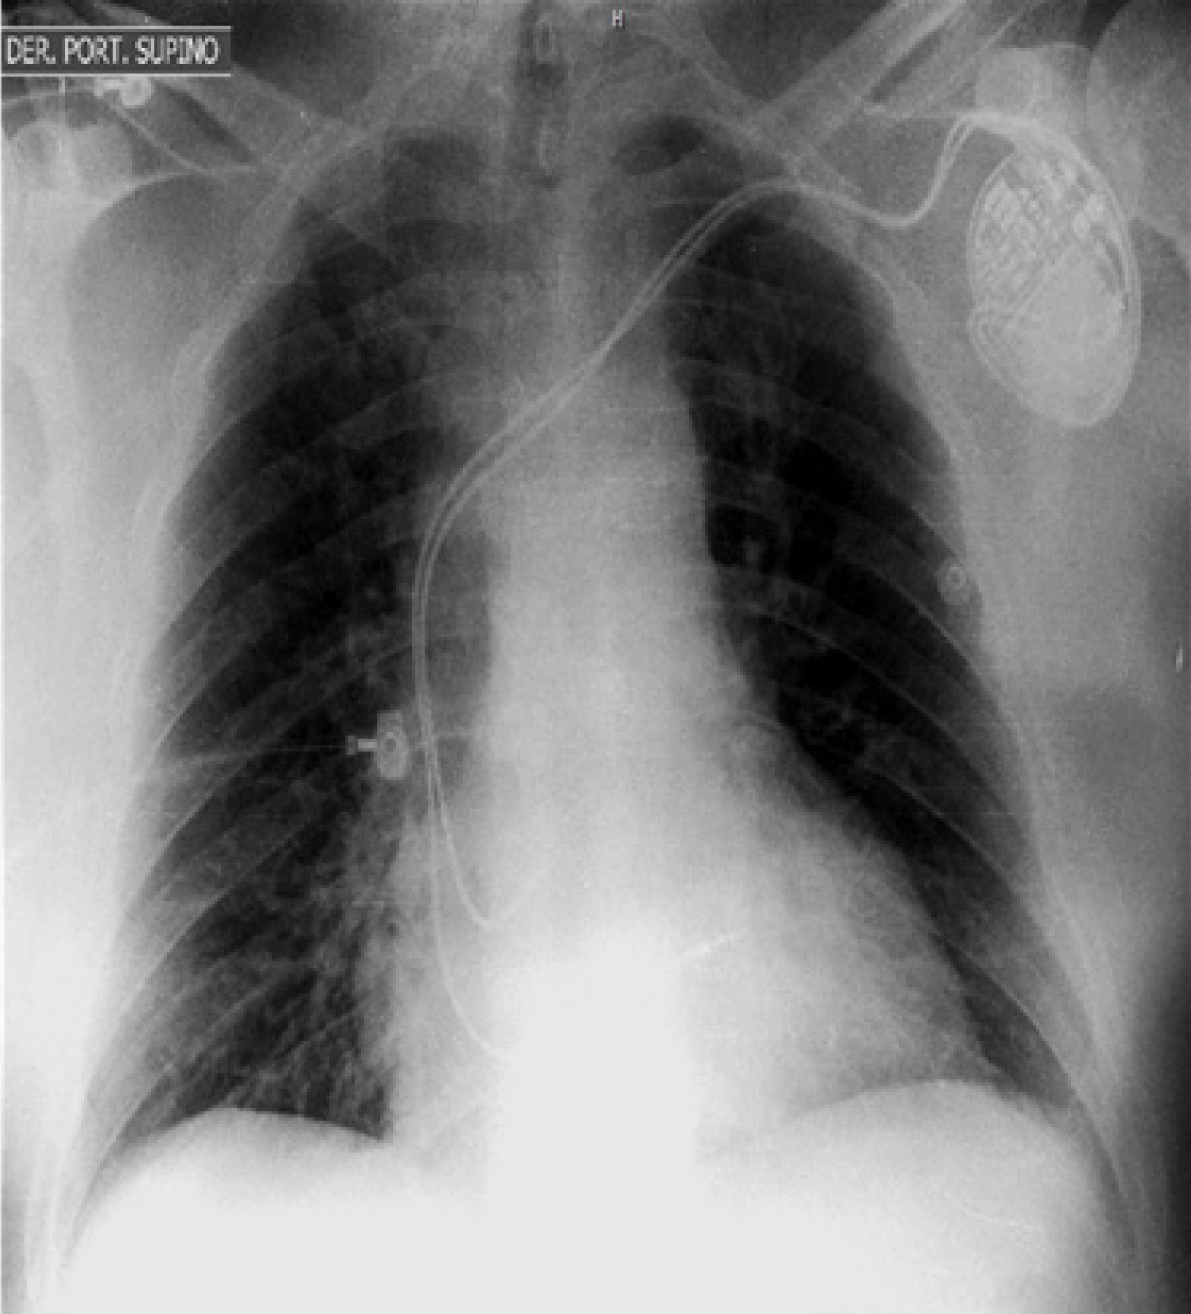

Figure 2: Chest X-ray after pacemaker implantation.

Through a cutaneous incision in the left deltopectoral groove, we dissected the tissue planes until the left cephalic vein became visible. Direct vein punctures allowed for venous access and passage of two hydrophilic wires without difficulty. Fluoroscopy in anterior-posterior projection showed clear supraclavicular course of the cephalic vein. (Figure 1) A venogram confirmed anomalous drainage of the left cephalic vein into the ipsilateral external jugular vein. Subsequently, both wires were removed and the terminal portion of the cephalic vein was ligated to achieve hemostasis. Through a fluoroscopy/venogram guided axillary puncture using the modified Seldinger technique and the retained wire technique, double central vein access was secured, allowing the passage of right atrial and ventricular leads, which were subsequently connected to a dual chamber pacemaker and implanted without complications in a usual pre-pectoral position. The patient was discharged from the hospital the next day after chest X-ray confirmed proper lead placement and device interrogation documented adequate sensing and pacing parameters for both leads. (Figure 2) After one week of follow-up, the device was functioning properly and the incision showed normal healing without evidence of infection.